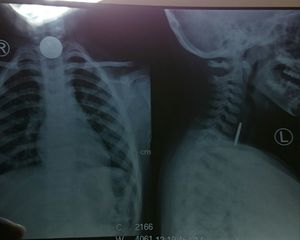

Koroalcoin

Emergency

Radiology

Foreign body lodges in oesophagus ?